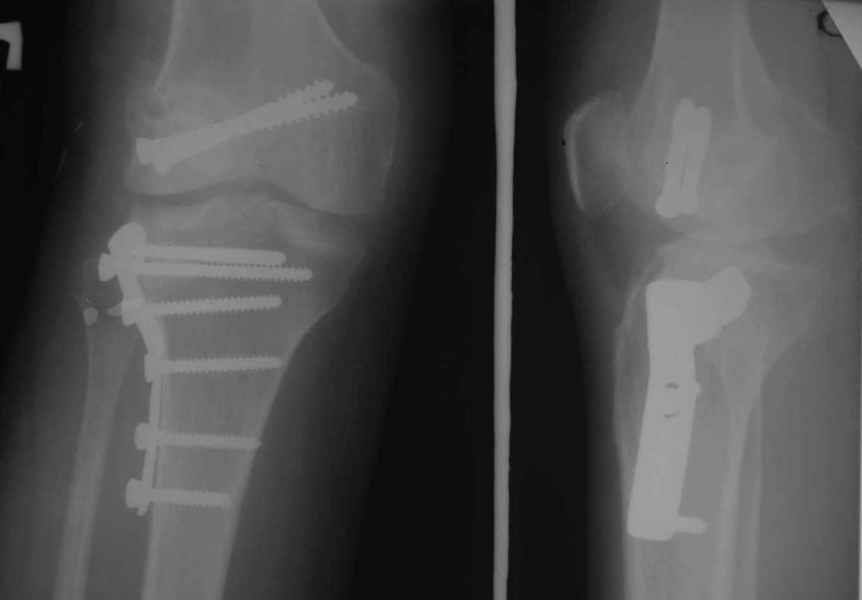

Тут ситуация совсем другая. Деформация не около-, а самая что ни на есть внутрисуставная. Покорректировать внешний вид конечности путем остеотомии дистального отдела бедра и high tibia (плюс или минус клин, одномоментно-постепенно, аппарат-пластина-стержень - дело третье) не сильно сложно, но это не решение проблемы. У больной, по

сути отсуствует латеральный отдел коленного сустава, что требует костно-пластических вмешательств непосредственно на артикулирующих

поверхностях.

Может быть, целесообразней сразу протез, чем тот же протез, но после сложных, но сомнительно результативных операций типа замещения алломыщелком, моделирующих резекций и т.п.? Ну и в любом случае движения лучше бы разработать получше до любой операции.

Деформация не около-, а самая что ни на есть внутрисуставная.

-Деформация оси сустава может быть варусной или вальгусной, причины - структурные изменения в латеральном -или медиальном отделе сустава (переломы, патология зон роста, дисплазии, дегенеративные процессы) результат лечения внутри- или внесуставного перелома и восстановление оси обуславливается анатомичностью репозиции и адекватностью фиксации. Нередко в запущенных -неправильно срасшихся unicompartmental внутрисуставных переломах восстановление оси и опороспособности достигается периартикулярными

остеотомиями...

- *как разбитую чашку не клей - все равно новой она уже не станет*, - поэтому при подтверждении некроза мыщелка бедра в сочетании с деструкцией тибиального плато, артропластика остаётся единственной альтернативой для восстановления функции и опорности ноги.

Сравни состояние артикулирующих поверхностей в представленном тобой примере и обсуждаемом случае.